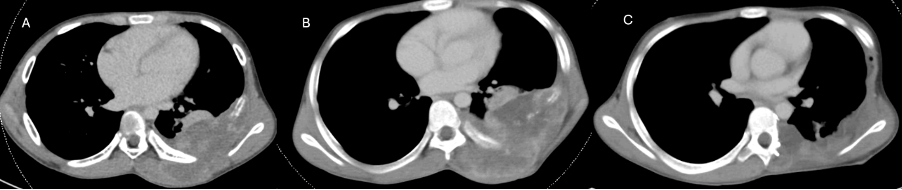

Two months later, the child presented with three episodes of seizures of generalised tonic-clonic semiology. CT scan of the head revealed a 2-cm enhancing lesion in the right frontal region with perilesional oedema, most likely representing a metastatic focus (Figure 1). A meningioma was also considered in the differential diagnosis; however, the patient’s young age and the absence of any syndrome typically associated with pediatric meningiomas made this less likely. CT thorax revealed multiple soft tissue lesions at the surgical site, the largest 2.3x2cm and an intraspinal deposit at the T6-7 level, suggestive of local recurrence (Figure 2). There were no skeletal metastases on the bone scan.

Figure 2: CT Thorax images at various time points. A-At presentation, B-Prior to surgery, C-At recurrence